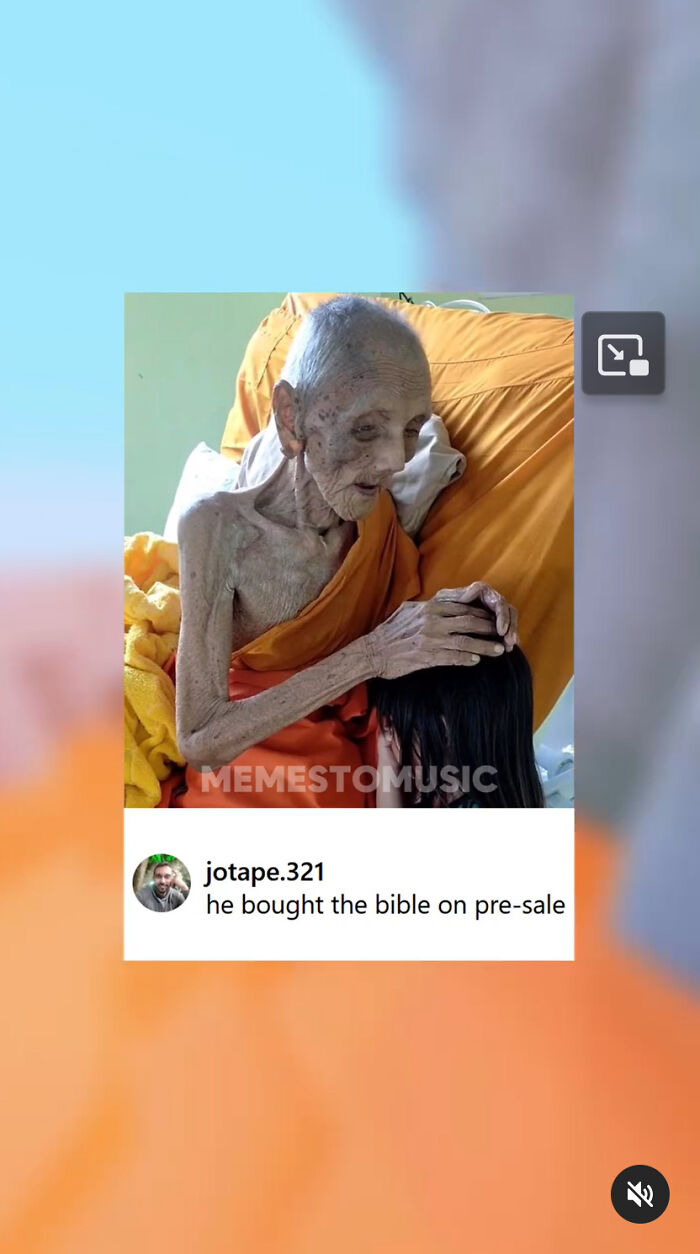

I've Seen A Few Bedridden Emaciated Buddhist Monks In Southeast Asia. Wondering What Sort Of Medical Condition They May Have? They Seem To Live Off An Extreme Caloric Deficit, And It Also Appears As If An Ascetic Lifestyle Is Honored